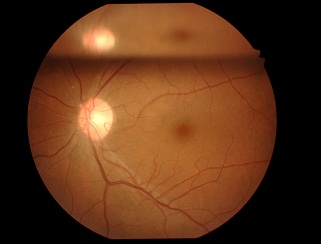

黒目(角膜)から入ってきた光は、目の奥の方のフィルム(網膜)に当たります。網膜は一つの束(視神経)になって、最終的には脳ミソにつながり、「物が見える」という事になります。

図の赤矢印の部分は視神経乳頭と言って、網膜が集まって束になる部分なのですが、実はこの部位のみ光を感じ取ることはできないのです。

写真だと水色の部分が視神経乳頭(マ盲点)になります。ちなみに、物を見る中心部の網膜は黄斑と呼ばれ、オレンジの矢印に当たります。

マリオット盲点以外の部位が欠ける場合は病気となるのですが、視野が欠ける代表的な疾患として、緑内障があります(日本人の失明の原因の第一位)。

マリオット盲点を認識しづらいのと同様に、実は、緑内障で視野が欠けた場合も初期の段階では気が付きにくいのです。(初めて病院に来る時には、末期だったんてことがよくあります。)